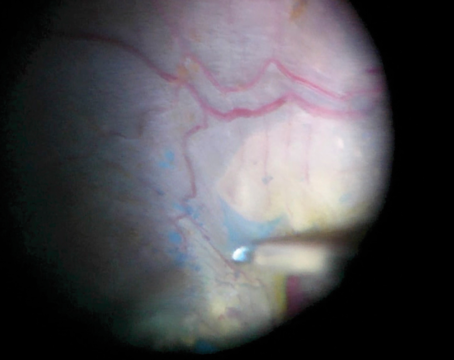

Surgical tips for single 27-gauge vitrectomy for navigating through tight surgical planes in tractional retinal detachments.